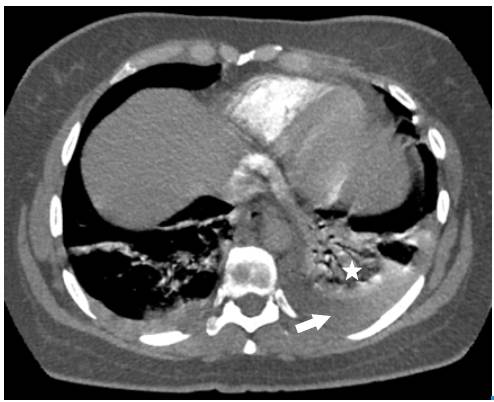

Surprisingly, after initiating anticoagulation and other general treatment measures indicated for pulmonary thromboembolism, and about three days after her hospitalization, the patient required increased oxygen flow through nasal cannula, her chest pain worsened, and presented with dyspnea, fever, leukocytosis, tachycardia, and tachypnea. Control para-clinical exams were requested, revealing high C-reactive protein and a significant increase in leukocytes at neutrophils expense. A new chest tomographic evaluation was performed, in which wedge densities were identified in the middle and lower right lobes and in the lower left lobe, as well as an aerial bronchogram of the right lower lobe and bilateral pleural effusion (Figure 3 and 4). No blood cultures or sputum cultures were performed.